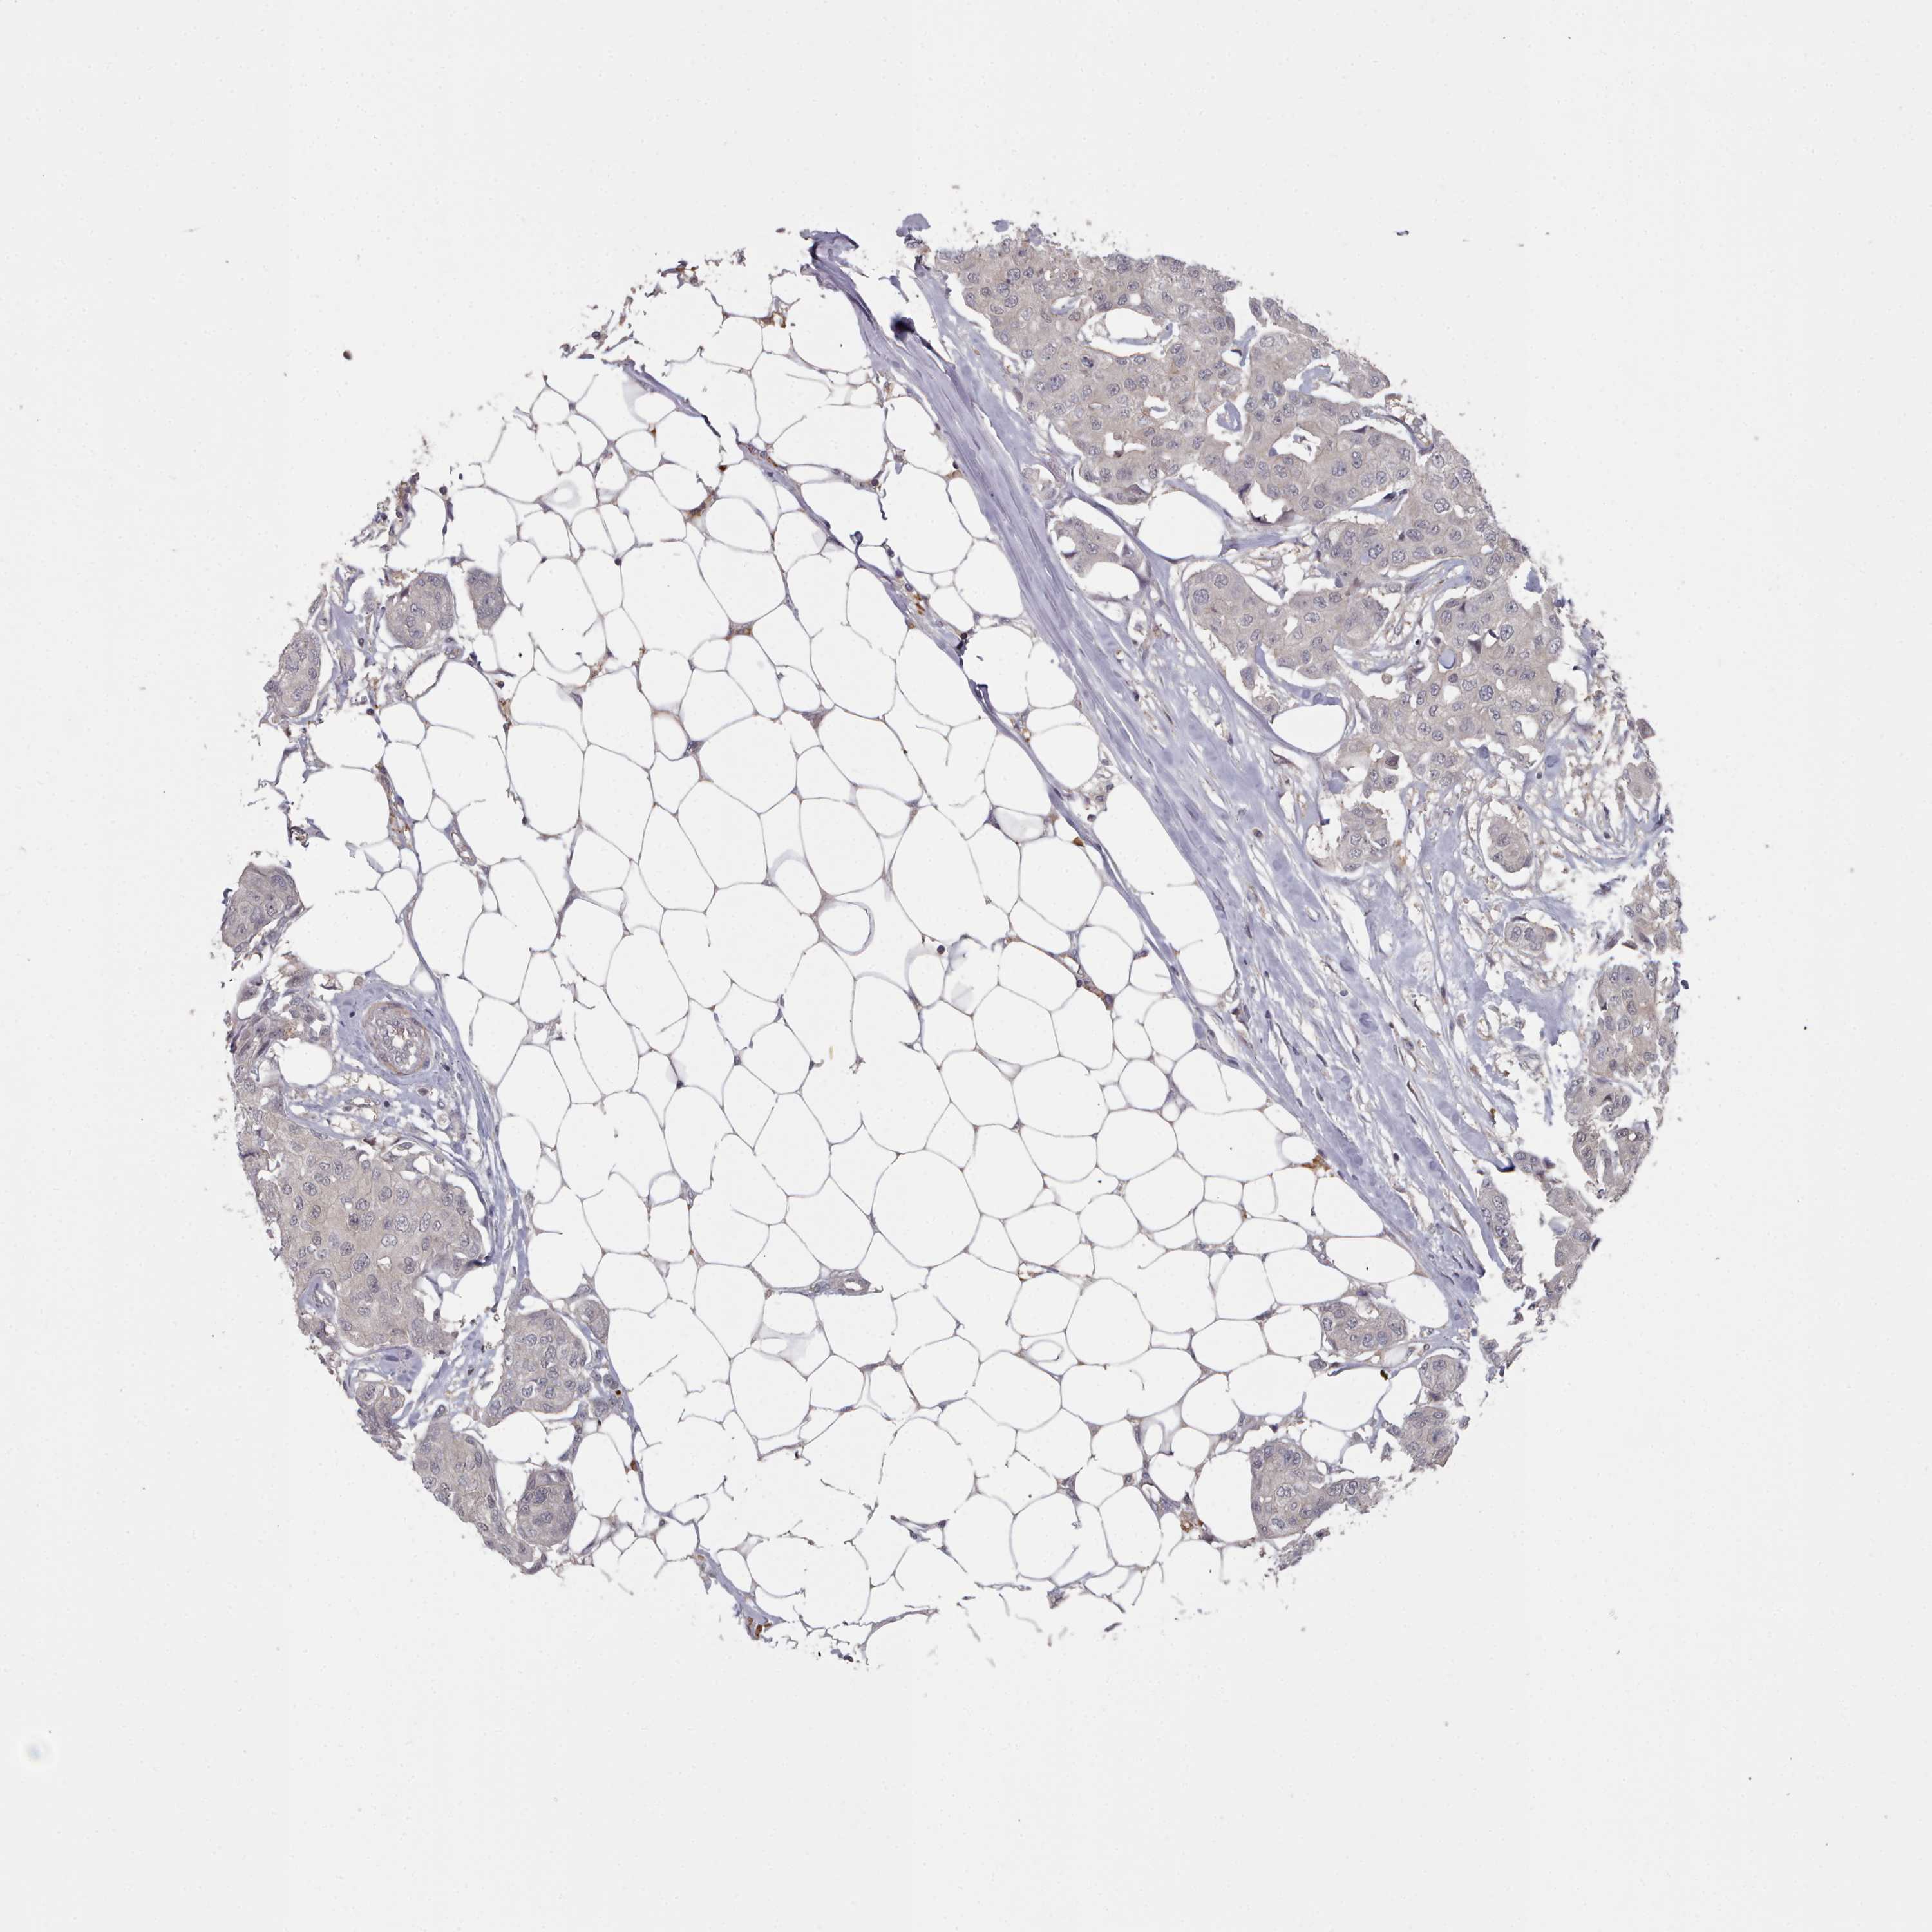

BRCA TCGA BRCA VALIDATION PROTEIN EXPRESSION